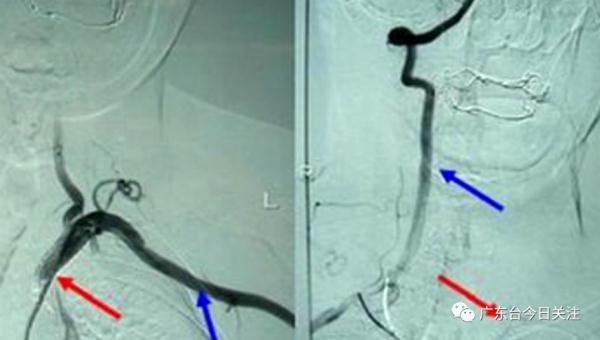

经医院初步评估,小美的症状符合脑卒中,进一步完善头颈CTA检查,发现小美得了一种名叫“东方美女病”,学名称为“大动脉炎”的疾病。

“东方美女病”好发于东亚女性,一般是30岁以下,目前病因不详,一般考虑是感染后诱发免疫调节,免疫应答异常,累积到大动脉血管炎造成的。